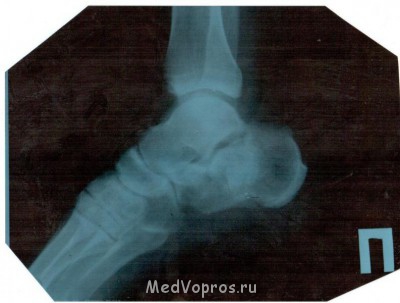

8 августа 2011г упал со стремянки результат оскольчатый перелом пяточной кости. раскажите как проходит заживление. наш хирург не чего не говорит. сказал три месяца лангеты и всё. самочуствие ноги. когда опускаю она стаёт красно фиолетовая бегают по ней мурашки отикает к вечеру жгёт в районе перелома дёргает как током бьёт. сколько времени на реабилитацию снимок 12 недель 4 месяц хожу на одной локтевом костыле

Перелом пяточной кости